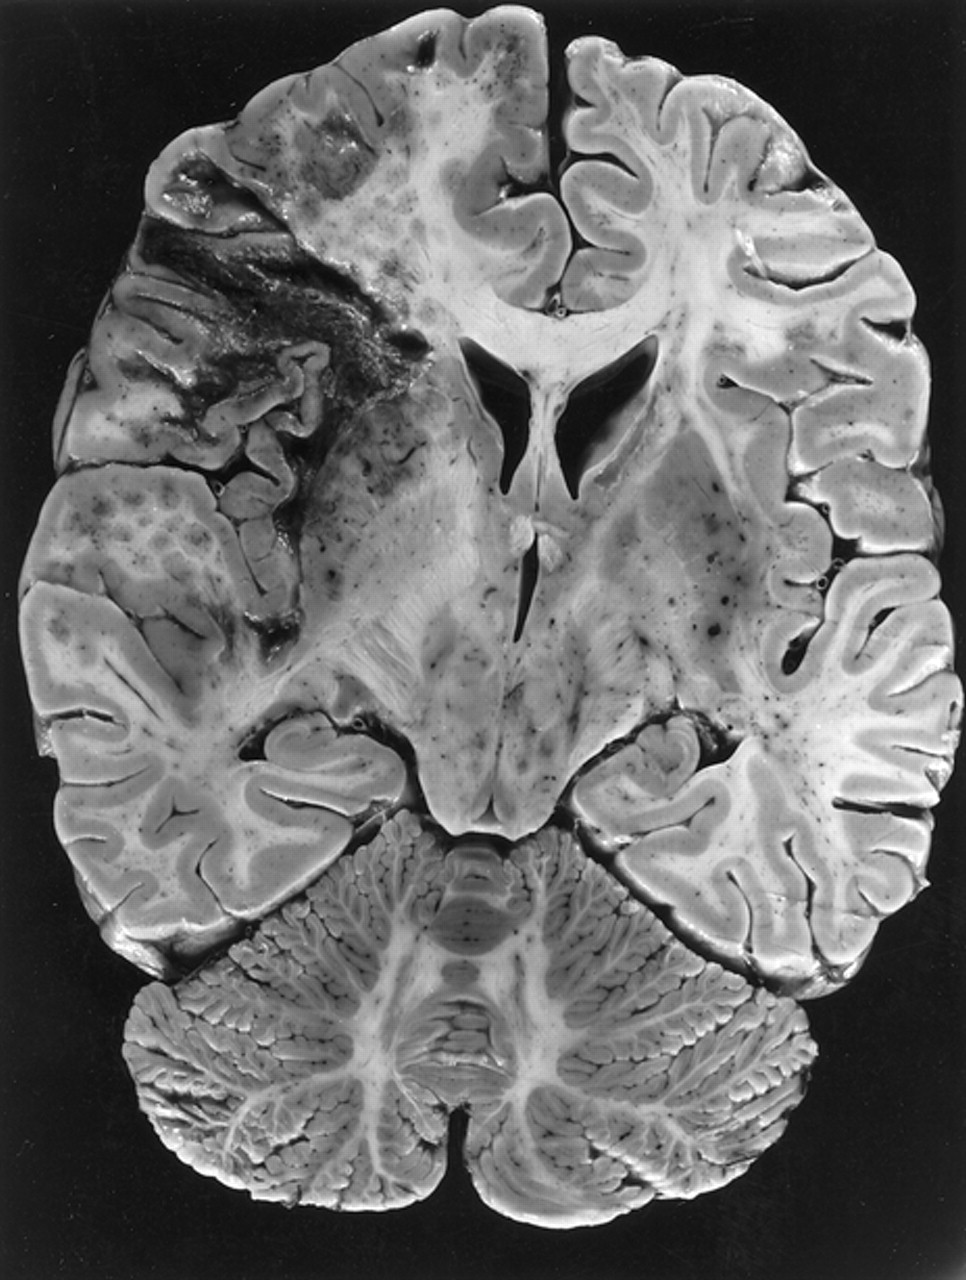

Pneumococcus

Bacteria, respiratory droplets

Bacteria, respiratory droplets- Symptoms: Sudden onset of fever and fatigue, cough, pleuritic chest pain, blood-tinged sputum. Pneumococcal meningitis may present as a stiff neck, headache, lethargy, or seizures.

- Complications: similar to Hib, ear infections, cellulitis (skin infections), infectious arthritis (joint infections), bacteremia (blood infections), meningitis (stiff neck, fever, photophobia, confusion)

- Deaths/Statistics: 900,000 Americans get pneumooccal pneumonia each year and 5-7% die from it. There were 3,300 deaths in the U.S. from pneumococcal meningitis and bacteremia in 2012. About 3,000 cases of pneumococcal meningitis occur each year and of those cases 10% will die from the infertion.

- Pneumococcus is the most common cause of bloodstream infections, pneumonia, meningitis, and middle ear infections in young children.

- As Hib, antibiotics can kill pneumococcus, but infants are highly susceptible and can be asymptomatic, developing fever to death in a matter of hours.

- I can’t emphasize this enough, there is no time to save a baby from Hib and pneumococcal bacteremia or meningitis. I have seen a baby in the nursery seem fine at 9 am and in a coma at 12 noon.